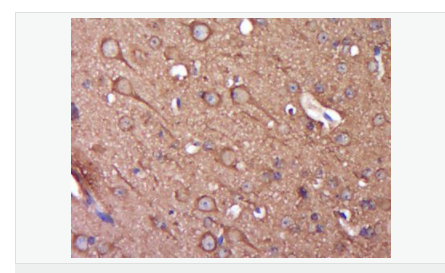

image.png